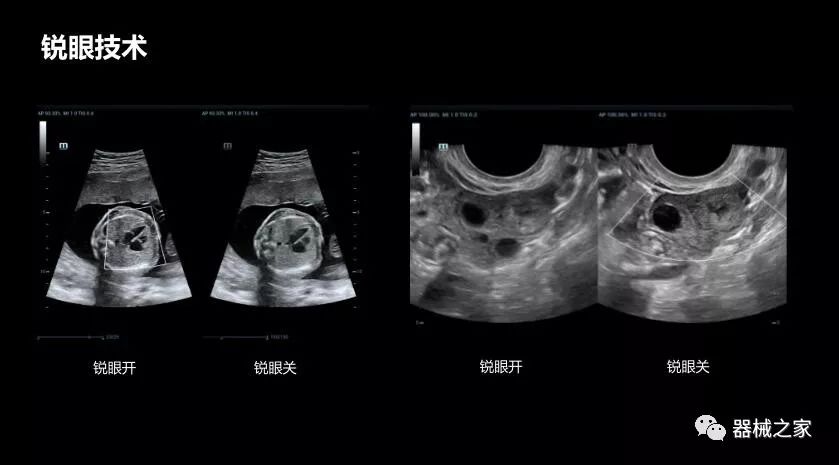

銳眼技術

做胎兒心臟檢查的時候,如果是聲窗不好的孕婦,很難看清胎兒心腔 。女媧Resona 8的銳眼技術能很好的優(yōu)化心腔內(nèi)的噪聲,讓胎心結構完美的呈現(xiàn)。